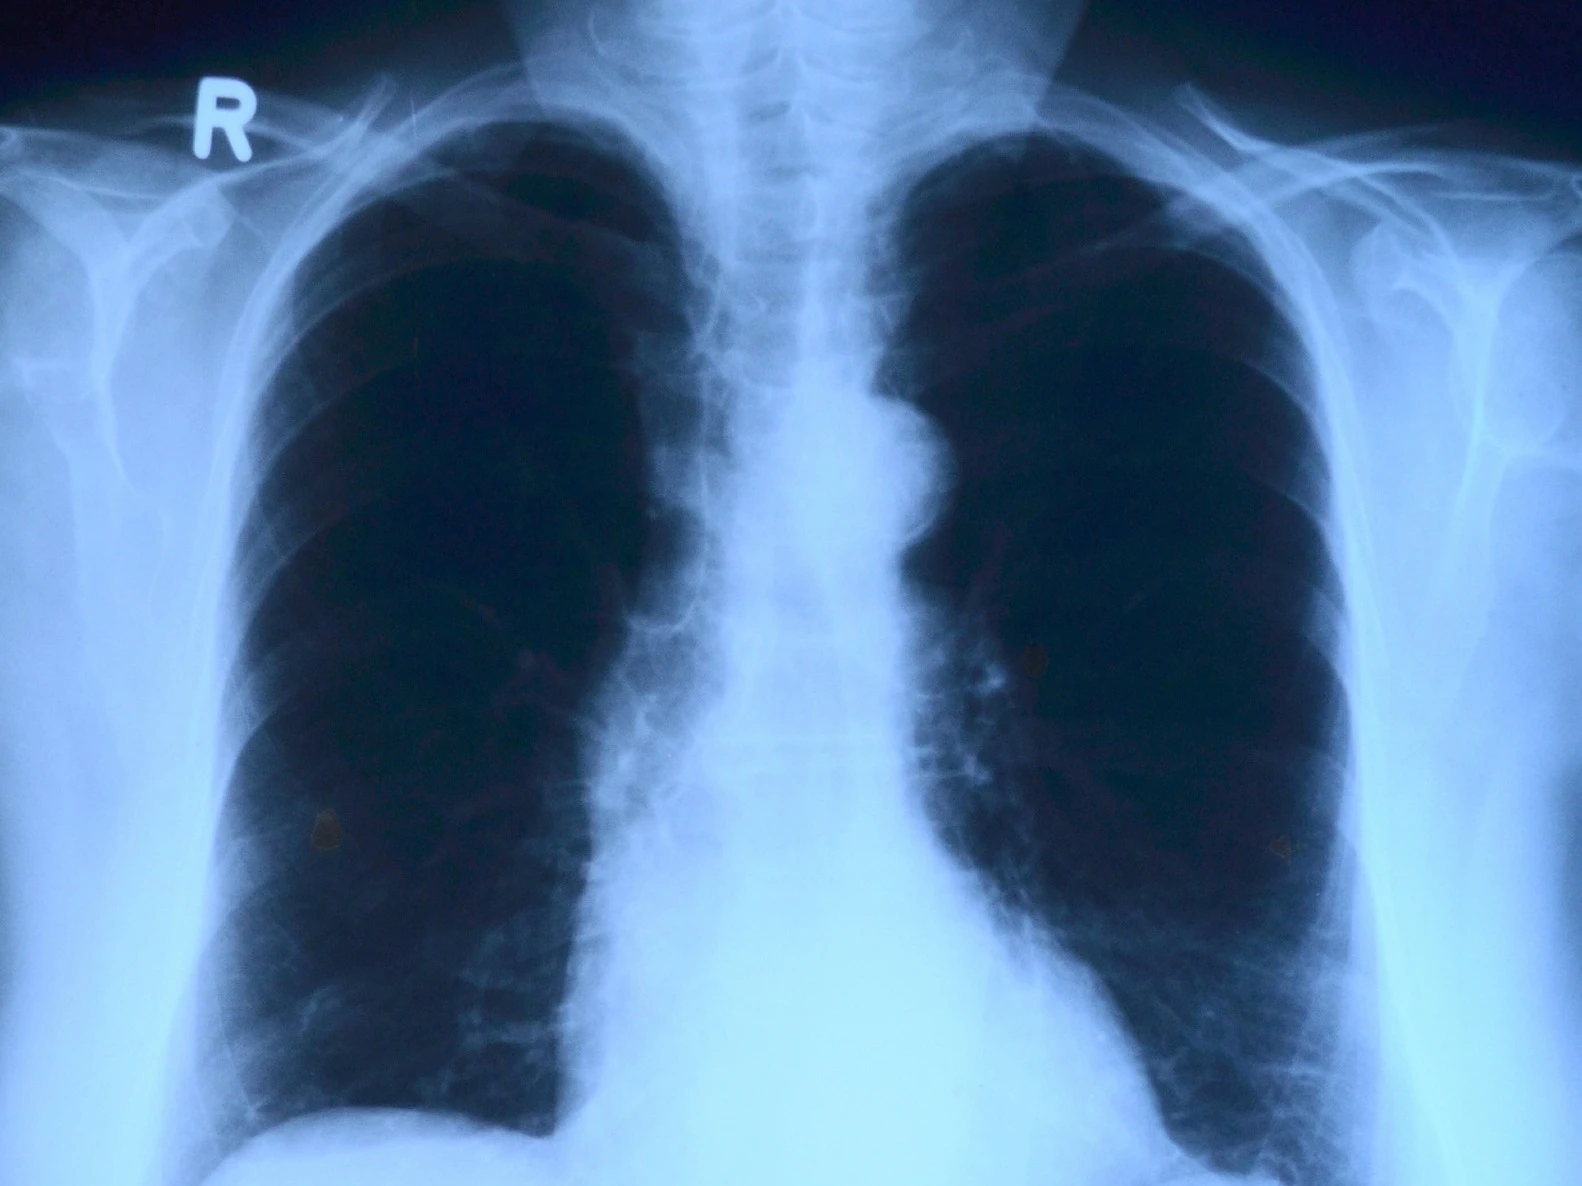

zdjęcie RTG,